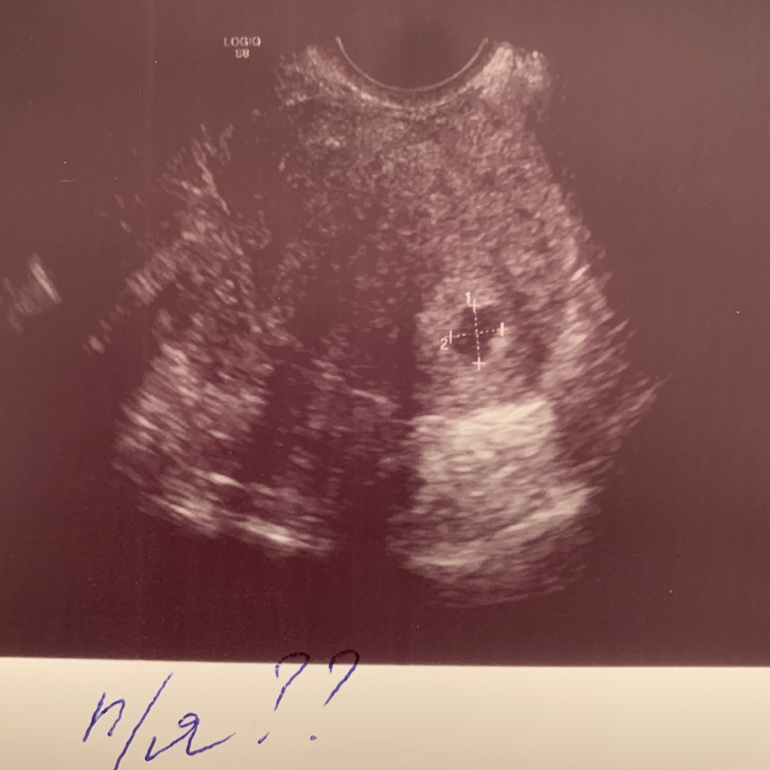

На УЗИ попала в тот же день. По результату: эндометрий - 21мм. В верхней трети полости матки, справа, лоцируется гипоэхогенное выключение вытянутой формы с четкими неровными контурами, размерами 9x8мм. Желтое тело слева 20 мм. Трубы не просматриваются.

Что это за выключение без заключения Г мне сказать трудно. За расшифровкой пойду завтра к тому же Г. по ДМС и к своему врачу по невынашиванию.

Г и врач УЗИ придерживались мнения, что больше похоже на маточную Б.